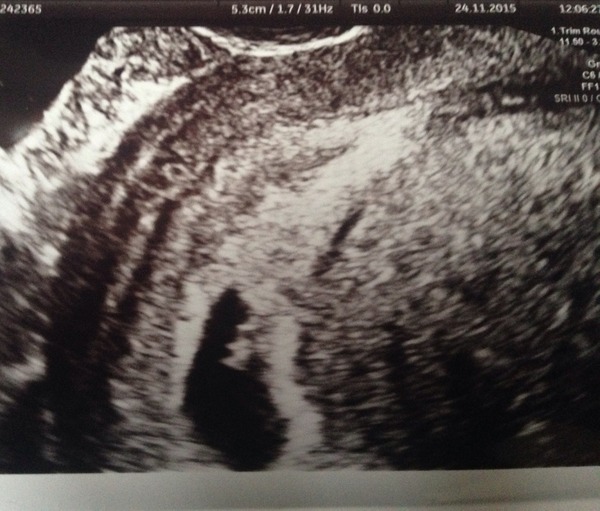

Peyia · 25/11/2015 18:56

Forgot to attach bean (6 weeks)

Peyia love ur pic , baby looks like a we gummy bear , can see arms and legs forming ! Amazing X

Glad all is well peyia, so lovely that you got to see your little bean!

Gx that's exactly what I said. It looks like a little gummy bear Smile